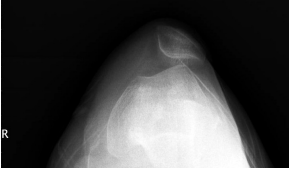

27 23 歲女性,自訴一年前跌倒以致右膝損傷,右膝酸痛反覆持續至今,上下樓梯時酸痛加重,蹲下困 難,膝關節軸位,X 光片如圖示,請問診斷為何?

(A)股骨髁上骨折 (B)新鮮髕骨脫位 (C)股骨髁間骨折 (D)髕骨習慣性脫位